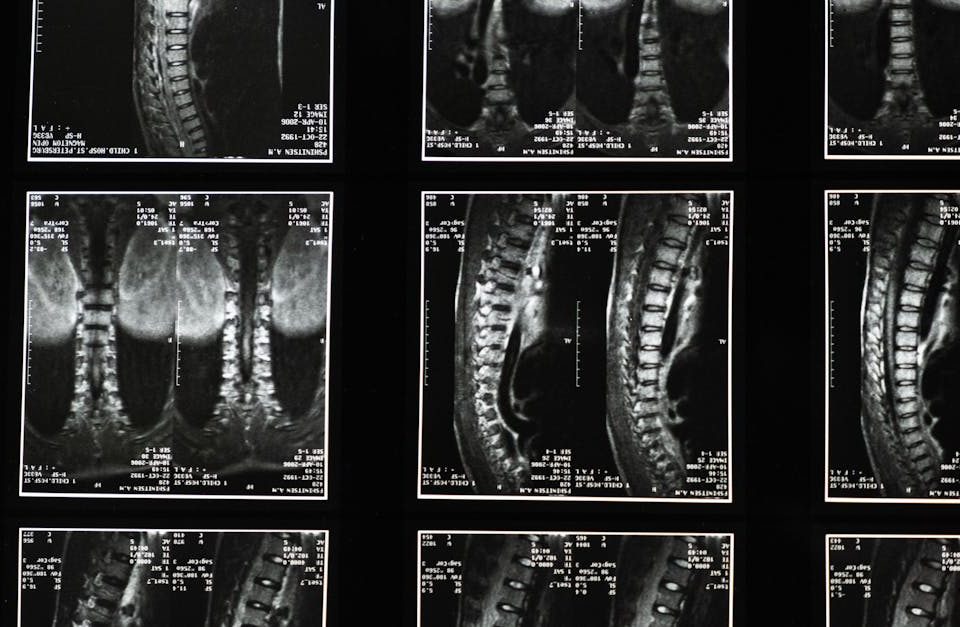

Sténose spinale : pourquoi choisir la décompression neurovertébrale ?

EN BREF La sténose spinale est un rétrécissement du canal rachidien qui peut causer des douleurs et des gênes. La décompression neurovertébrale est une méthode non […]

Décompression neurovertébrale : une alternative non chirurgicale au traitement du bombement discal

EN BREF La décopression neurovertébrale est une méthode innovante pour traiter les bombements discaux sans recourir à la chirurgie. Ce traitement non invasif, accessible à Paris […]

Décompression neurovertébrale : une alternative non chirurgicale pour traiter la sténose spinale

EN BREF La décompression neurovertébrale est une technique non chirurgicale visant à traiter la sténose spinale en soulageant la pression sur les disques intervertébraux. Accessible à […]